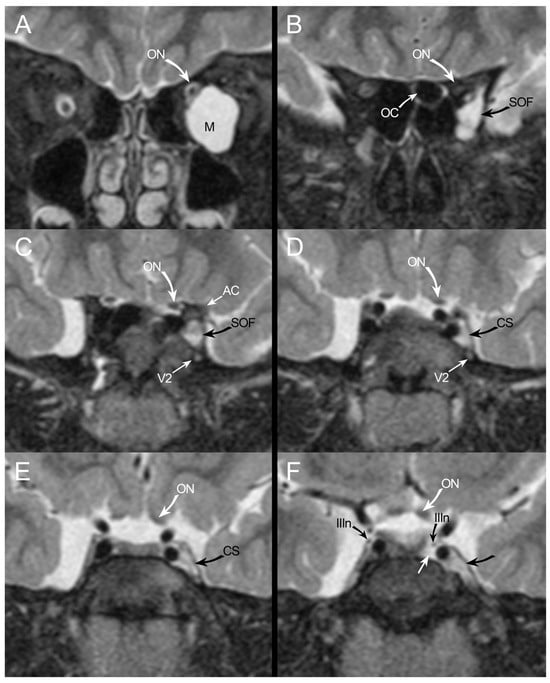

3.1. Case Report